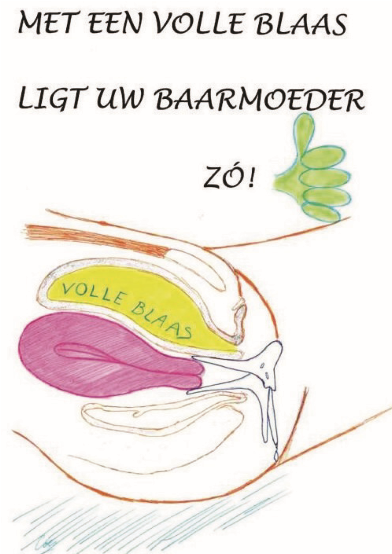

5 Plaatsing van het embryo (embryotransfer)

De embryotransfer vindt plaats onder echoscopisch zicht via de buik. Dit betekent dat de plaatsing met de echo via de buik gevolgd wordt om zo nauwkeurig mogelijk de juiste plaats in de baarmoeder te bepalen. Om het goed te kunnen zien, is een gevulde blaas noodzakelijk (zie 1e tekening).

Figuur 8. Volle blaas voor embryotransfer.